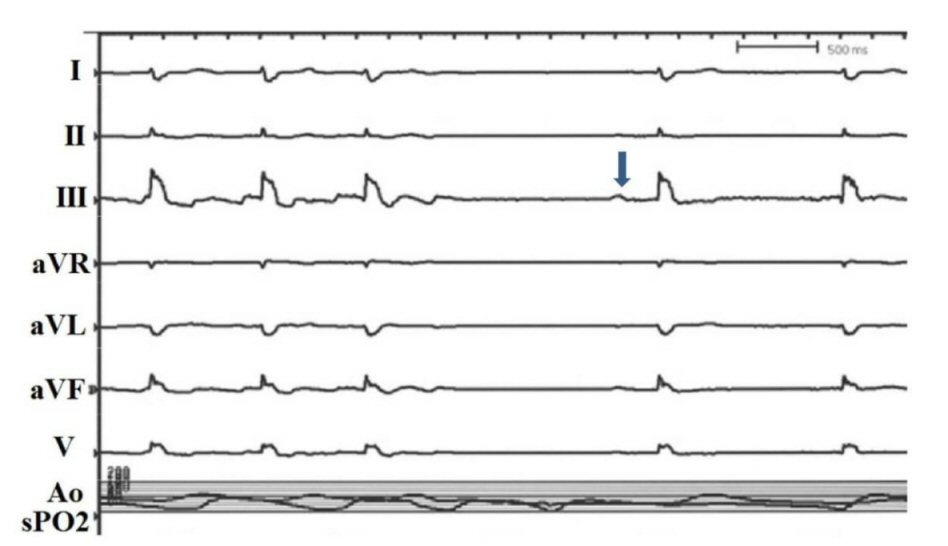

A 77-year-old male with a history of coronary artery disease, prior coronary artery bypass graftsurgery, bioprosthetic aortic valve replacement and paroxysmal AF presented with worsening shortness of breath on exertion for 1day. Patient did not have any chest pain, palpitation, dizziness, diaphoresis or nausea. Physical examination was significant for normal temperature, blood pressure of 110/70 mm Hg, irregular heart rate of 88 - 100 bpm, respiratory rate of 14/min with oxygen saturation of 95% at room air. Heart sounds were irregular with grade 1/6 ejection systolic murmur at right second intercostal space. Lungs were clear to auscultation. There was no evidence of edema of the extremities, and the rest of the physical examination was normal. His troponin I, serum potassium and magnesium were normal. He had an insertable loop recorder (ILR), (Reveal LINQ LNQ11Medtronic) which showed a new AF event for 36 h. The patient was brought to cardiac catheterization laboratory for coronary angiography with a view to PCI if necessary, and direct current cardioversion. Along with patent grafts and known disease in the respective coronary arteries, new critical and severe stenotic lesions involving the ostium and distal segment prior to the posterior descending branch of large dominant RCAwere detected (Fig. 1). These lesions were addressed in a stepwise manner with standard interventional balloon dilatation techniques. Interestingly, the patient’s rhythm converted to atrial flutter which converted to sinus rhythm upon PCI of the proximal ostial lesion restoring Thrombolysis in Myocardial Infarction (TIMI) grade 3 flows through the previously occluded segment as well as throughout the remainder of the vessel (Fig. 2, 3). He has remained free from any symptoms in sinus rhythm for more than 9 months as confirmed by regular follow-up of ILR.

![]() Click for large image | Figure 3. Conversion of atrial fibrillation to normal sinus rhythm during balloon inflation of the proximal right coronary artery (arrow). |